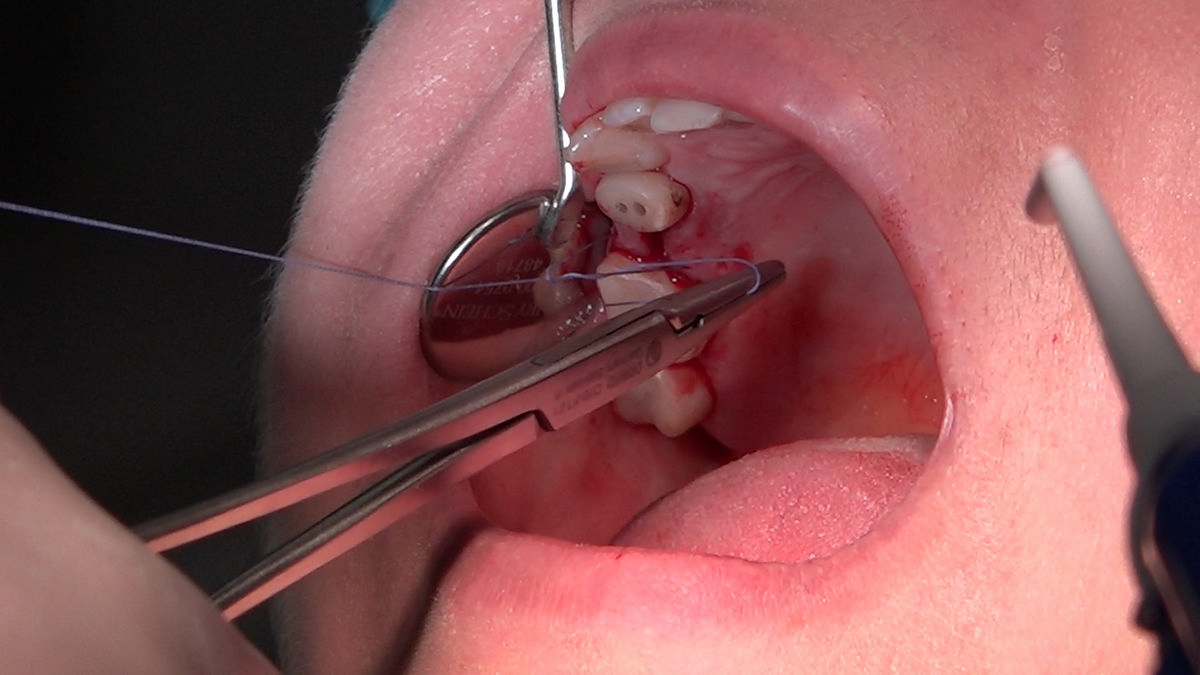

PRACTICULUM IMPLANTOLOGII - SEZON X - SESJA 4 - GRUPA B